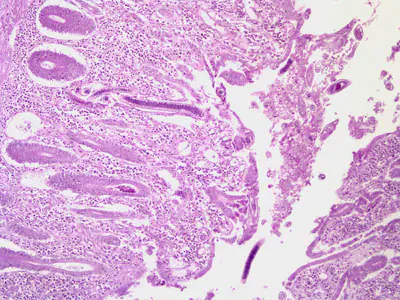

A huntsman killed a bear and prepared it for eating and freezing by cutting it into roasts, steaks, and grinding the trimmings. Later that same day, he ate a burger made from some of the fresh meat and cooked rare. Approximately two and a half to three weeks later, the hunter experienced fever, diarrhea, and muscle pain.